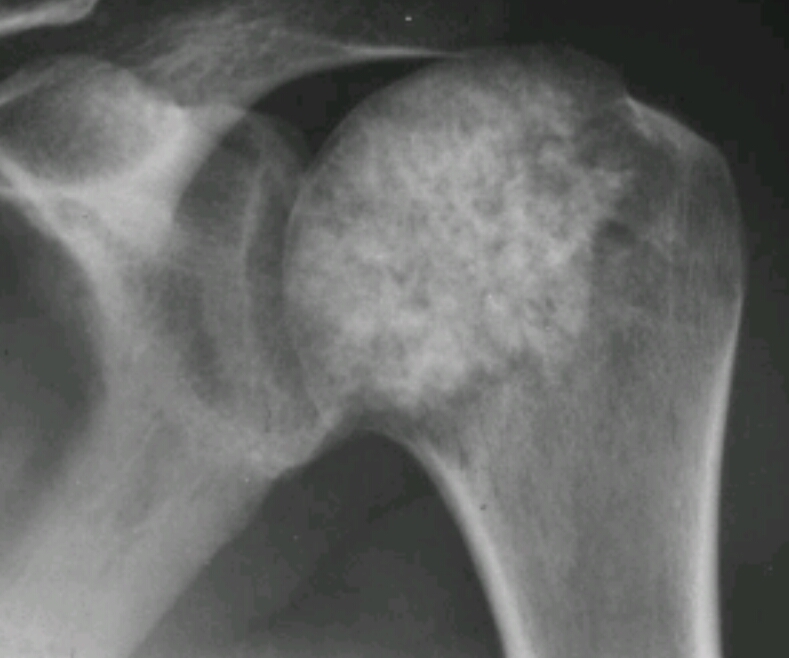

Stippled calcifications, popcorn like density, round oval area of demineralization, lytic destruction of proximal humerus

Chondrosarcoma